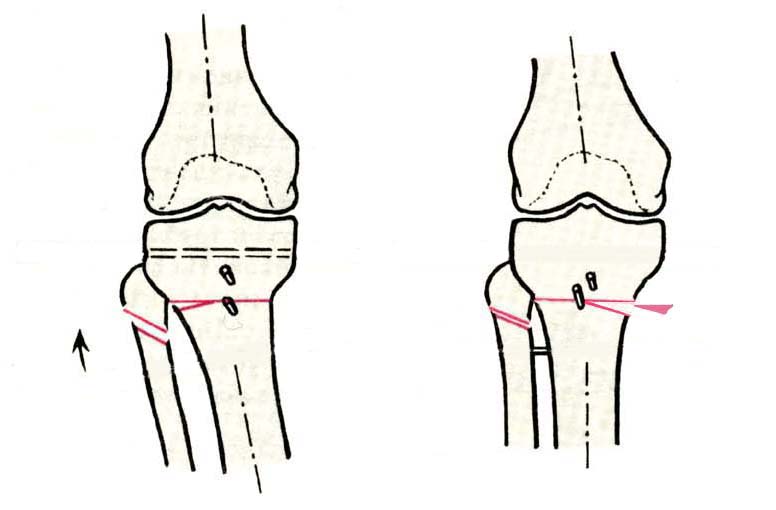

Дополнительными методами диагностики являлось измерение внутрикостного давления в зоне гипернагрузки и радионуклидные исследования нуклидами технеция. Применялись различные варианты остеотомий на различных сегментах. Для коррекции варусной-торсионной деформации:

высокие плюс, минус остеотомии большеберцовой кости,косая остеотомия малоберцовой. Для коррекции вальгусной деформации применялась плюс, минус надмыщелковая остеотомия бедренной кости. Фиксацию при высокой подмыщелковой остеотомии производили уникальной клинковой пластиной и тяговыми кортикальными винтами. Угол коррекции выставлялся

специальным угломером и направителем.

GBS> варусной-торсионной деформации: высокие плюс, минус остеотомии

GBS> большеберцовой кости,косая остеотомия малоберцовой.

Плюс, минус - это при одной операции? В смысле, и иссекали небольшой клин, и оставляли открытый с другой стороны?

GBS> остеотомии производили уникальной клинковой пластиной и тяговыми

GBS> кортикальными винтами. Угол коррекции выставлялся специальным

GBS> угломером и направителем.

>Плюс, минус - это при одной операции? В смысле, и иссекали небольшой

>клин, и оставляли открытый с другой стороны?

В зависимости от баланса связок, комбинировали (+-)остеотомии или производили полную

минус или плюс остеотомию